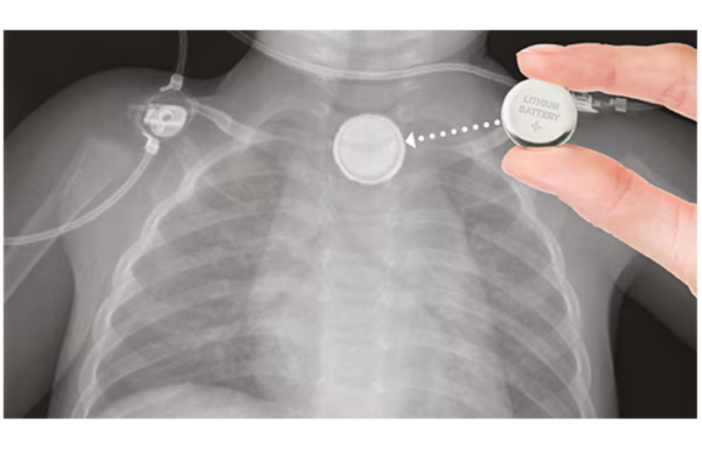

Button and coin cells are small round batteries for compact devices. Most every family uses them in watches, calculators, remote controls, and hearing aids. Unfortunately, this means button batteries and coin cells are in reach of almost every child.

Every button battery and coin cell holds an electrical charge. This may be the full power when new, or the residual charge after it runs down. These batteries transfer their current from one side to the other when in use.

Another child and another button battery can be a lethal combination, according to Child Accident Prevention Trust. Most times these batteries pass harmlessly through a child’s body after they swallow one.

But if the battery gets stuck in the food pipe that’s another matter. The battery charge reacts with saliva and forms caustic acid. This acid can burn through the food pipe to the main artery, with serious, even deadly results.